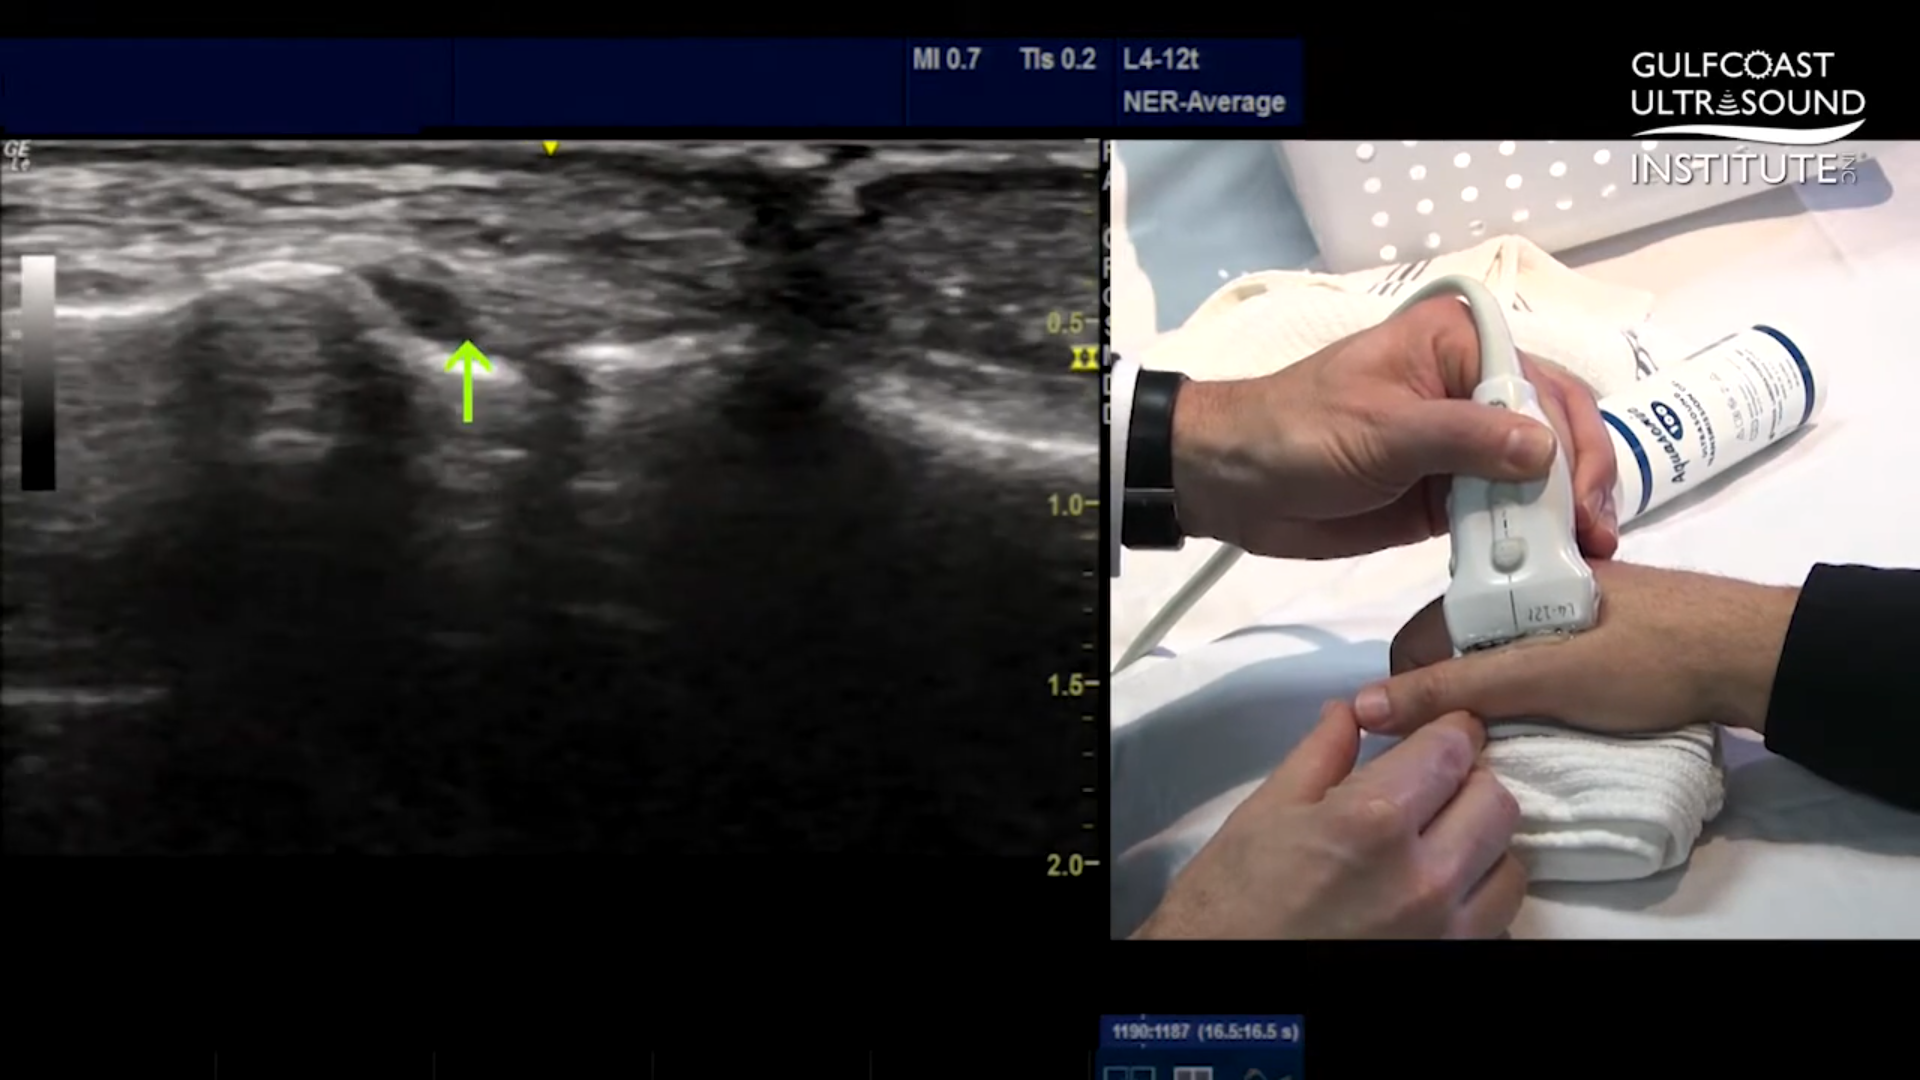

Key Visual Landmarks to Look For

During the scan, clinicians focus on specific bone contours and the position of the adductor aponeurosis. These landmarks are essential for distinguishing between a standard ulnar collateral ligament tear and a more complex Stenner lesion. A Stenner lesion occurs when the torn ligament becomes displaced and trapped, preventing natural healing. Ultrasound makes it possible to recognize this condition by observing how the ligament and surrounding tissues move or fail to move during the exam.

Using Dynamic Stress Techniques to Reveal Hidden Injuries

One of the most valuable aspects of ultrasound evaluation is the ability to perform dynamic testing. The tutorial highlights a stress technique that involves applying gentle pressure to the thumb joint while scanning. This maneuver can reveal fluid accumulation or joint widening that might not be visible at rest. In cases of partial or hidden ruptures, these subtle changes are often the key to an accurate diagnosis.